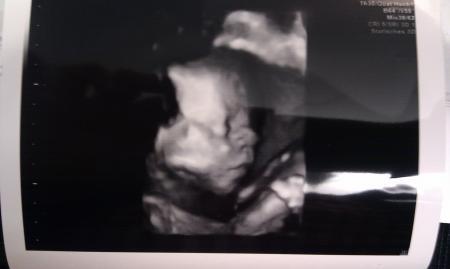

oh wie cool... freu dich mal,is echt cool:) hier mal n bild,ich war am montag bei der feindiagnostik. liebe grüße